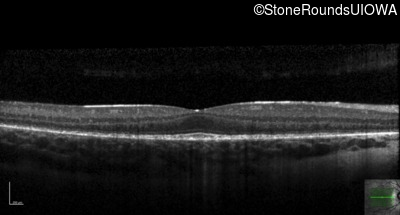

Age at visit: 11 years

OD OS

This 11 year old boy first had some fundus abnormalities noted during a routine eye exam at age 8. He remains asymptomatic. He has no difficulties seeing in dim light.